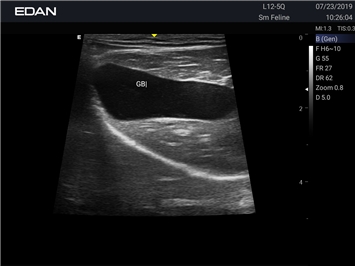

Ветеринарный ультразвук одним нажатием. Система Acclarix AX2 VET разработана с целью обеспечить бескомпромиссную производительность по доступной цене. Наличие уникальных двойных аккумуляторов в легком корпусе массой 4,5 кг из магниевого сплава позволяет системе Acclarix AX2 VET удовлетворять все потребности ветеринарных исследований, сохранив низкую стоимость.

EDAN Acclarix AX2 VET представляет собой специализированную ветеринарную ультразвуковую систему, сочетающую высокую производительность с доступной ценой. Благодаря продуманной конструкции и передовым технологиям, система обеспечивает качественную диагностику животных различных видов.

• Предустановленные протоколы для различных видов животных

B-режим, Двухмерное сканирование:

Да